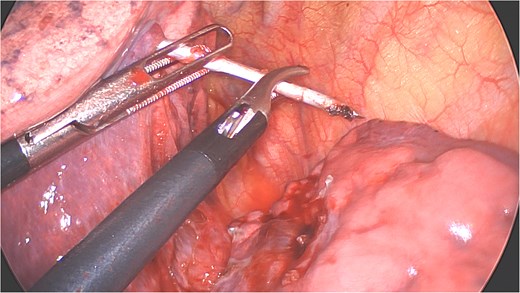

A clear minor pleural effusion and translucent scissural and para-aortic adhesions were visible. The adhesions of the pulmonary apex were released but no abnormality of the parietal pleura nor bone was visible. As the lung then collapsed, the pin became spontaneously visible protruding in the main fissure. As expected, the proximal part was in segment 2 and the distal half inside the apical segment of the lower lobe (S6) but it did not protrude outside of the parenchyma on either side (Fig. 4). The K-wire was easily removed by gently pushing back the parenchyma towards both extremities (Fig. 5). The pin seemed to be surrounded by a fine membrane that was coagulated at the visceral pleural entry point.

Distal part of K-wire stuck in segment 2 and the proximal part in the apical segment 6.

Extraction of the K-wire by pushing the parenchyma towards both extremities.